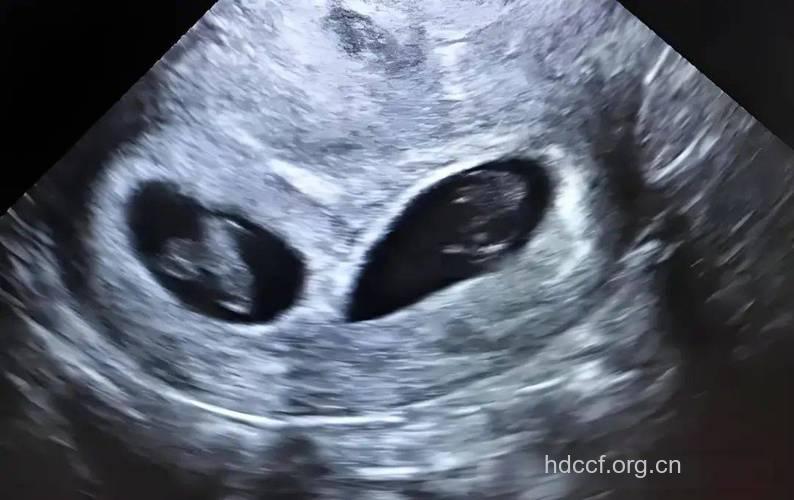

两个宝宝的手指和脚趾上现在都长出指甲了。他们的胳膊、腿、躯体也都在长大。有些宝宝甚至现在满头都是头发了。大多数宝宝都会在接下来的几周出生。也许能感觉到。

从36周开始,孕妇要每周做一次产前检查。由于胎动开始减少了,您要向医生学习如何测胎心和胎动。医生可以通过B超测量出宝宝的体重,不过在未来的几周中宝宝的体重还会发生变化的。同时孕妇在这几周中身体会越来越感到沉重,因此要注意小心活动,避免长期站立等。

妇女在怀孕时,胎动和胎心音能够反映出胎儿成长与健康的情况,测听胎动和胎心音也是产前检查的重要项目。一旦发现胎动不规律或胎心音微弱,就应立即采取必要的抢救措施,以防胎儿发生不测。